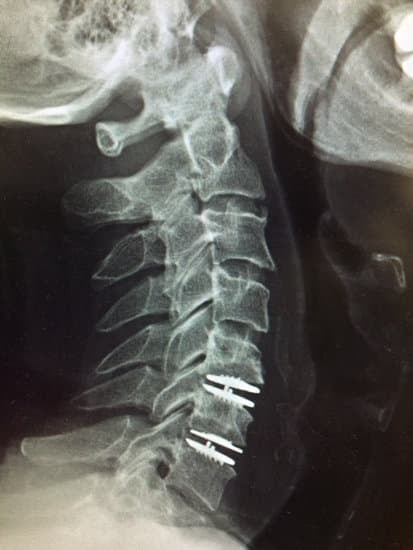

3) 수술적 치료 (심한 경우 필요)

✅ 미세현미경 감압술 (Minimally Invasive Surgery)

✅ 경추 유합술 (Cervical Fusion, 척추 고정술)

✅ 척수 감압술 (Laminectomy, 척추관 확장술)